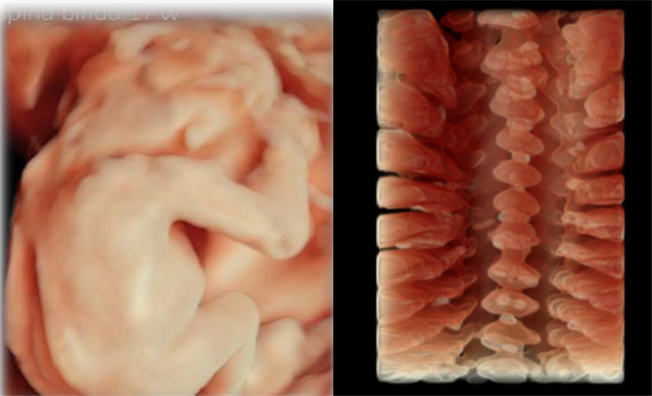

能够通过将更多、更细致的切面图像进行离线保存来观察胎儿唇、腭部位的发育状况,帮助医生诊断唇腭裂。“煊光”平台灵活的三维四维技术,可用于胎儿颜面部、中枢系统及脊柱异常的显示,通过细致的多切面成像分析胎儿的解剖结构及发育状况。

自动化技术可进行胎儿颈项透明层、颅内透明层的精准测量,评估早孕期胎儿染色体异常的风险,并对中孕期开放性脊柱裂的风险进行预测。

“煊影成像”技术可以清晰显示胎儿的内部结构,增加组织透明度调节,实现100级可调,从内到外,一览无余。在早孕、双胎等评估方面极具优势。